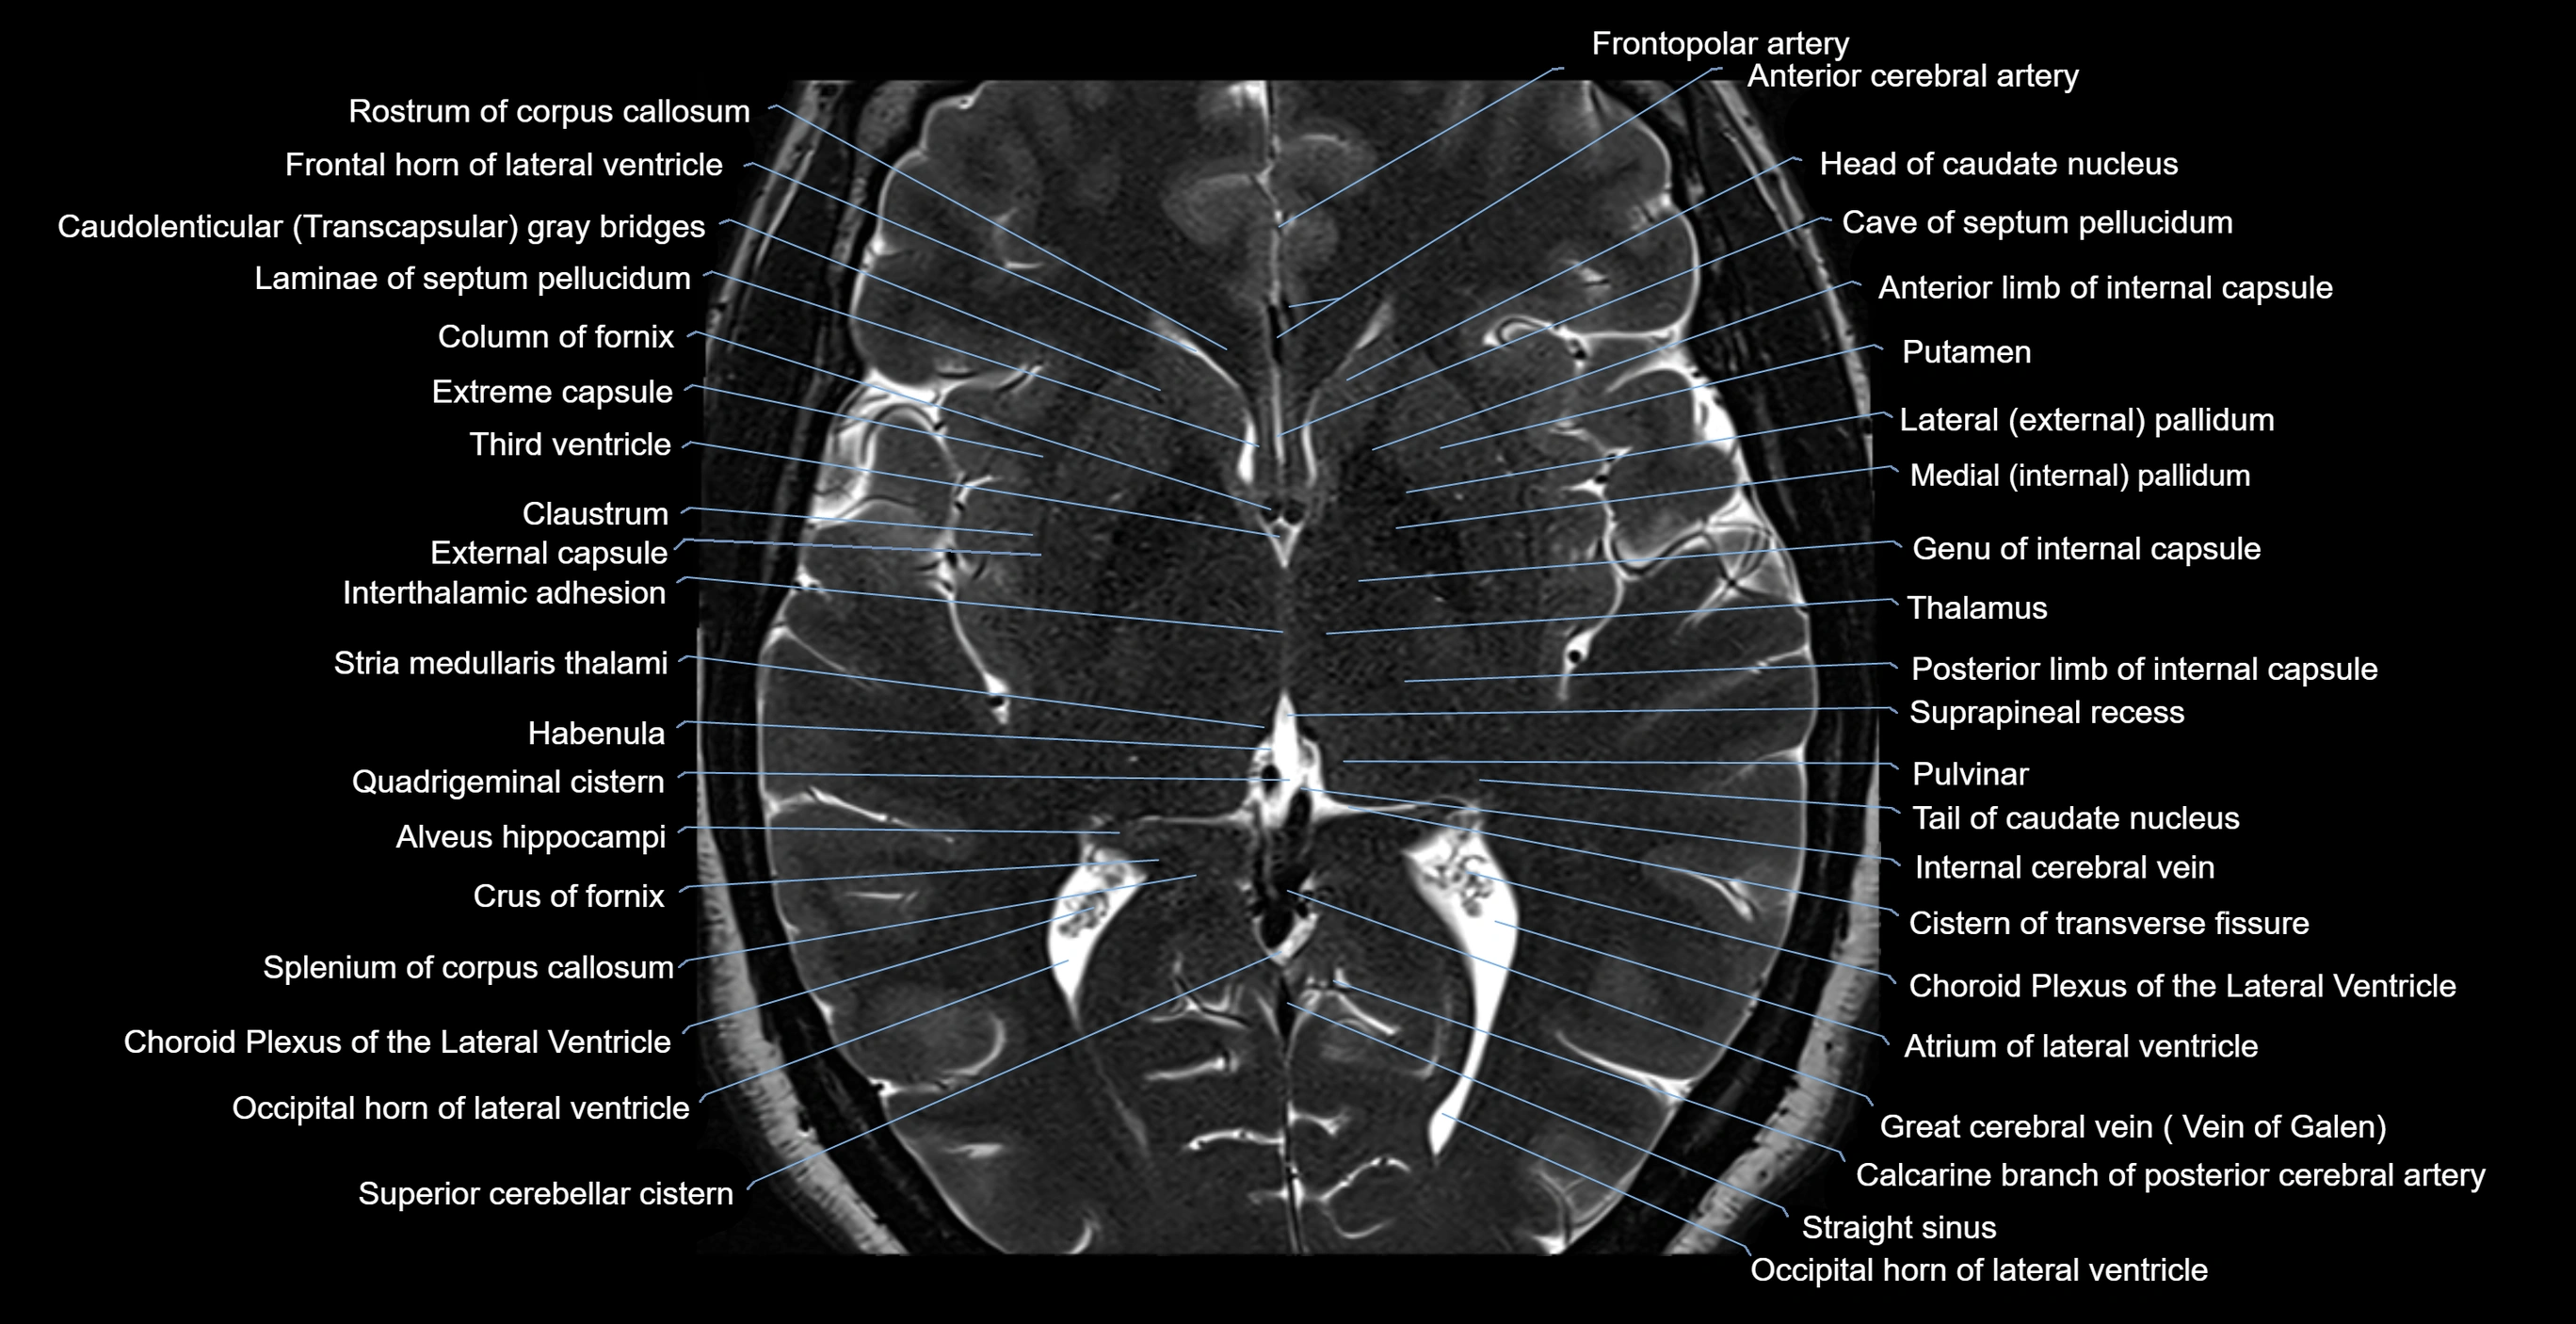

- Atrium of lateral ventricle

- Body of caudate nucleus

- Body of corpus callosum

- Body of lateral ventricle

- Calcarine branch of posterior cerebral artery

- Caudato-lenticular bridges

- Caudatolenticular gray bridges

- Cave of septum pellucidum

- Choroid plexus of the lateral ventricle

- Cistern of transverse fissure

- Column of fornix

- Crus of fornix

- Frontal horn of lateral ventricle

- Frontopolar artery

- Great cerebral vein

- Head of caudate nucleus

- Internal cerebral vein

- Interthalamic adhesion

- Lateral pallidum

- Medial pallidum

- Occipital horn of lateral ventricle

- Pulvinar

- Putamen

- Quadrigeminal cistern

- Rostrum of corpus callosum

- Splenium of corpus callosum

- Straight sinus

- Stria medullaris thalami

- Superior cerebellar cistern

- Suprapineal recess

- Tail of caudate nucleus

- Thalamus

- Third ventricle